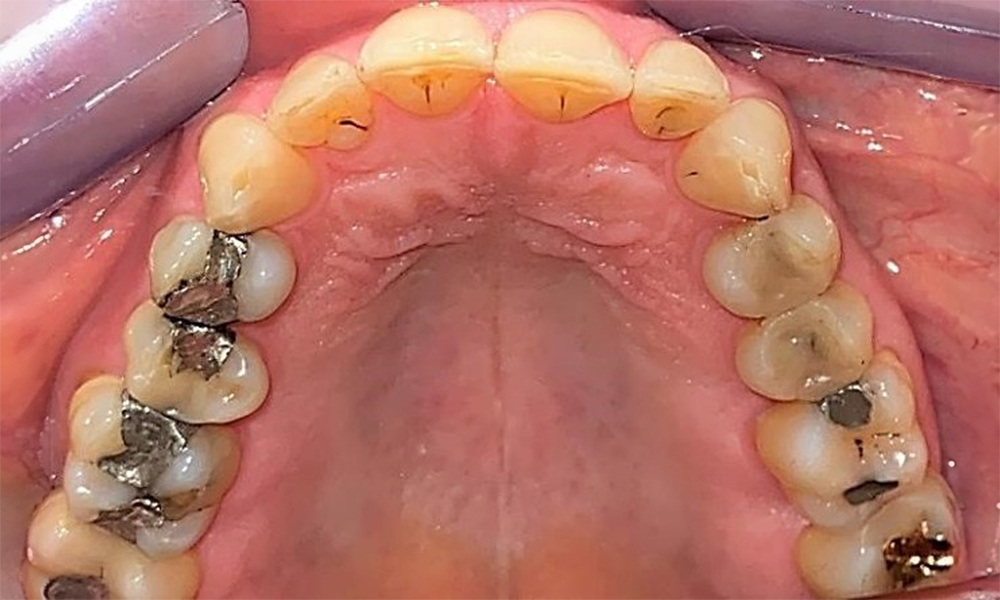

Оклузален изглед на горната челюст. Недостатъчна амалгамена пломба на 14 с маргинална празнина.

Фиг. 5 Оклузален изглед на горната челюст. Недостатъчна амалгамена пломба на 14 с маргинална празнина. © д-р Р. Крапф

Пациентът има пълно съзъбие с 28 зъба, което включва амалгамни и композитни пломби в областта на моларите и премоларите. На зъб 14 има видима клинична маргинална празнина. Зъб 27 има адекватна златна инкрустация. Налице са и генерализирани атриции и абразии. (фиг. 2, фиг. 3, фиг. 4, фиг. 5, фиг. 6)